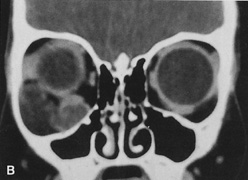

Fig. 6. Lateral orbitotomy through upper eyelid skin crease A. Photo demonstrating right globe ptosis present for more than 2 years. B. Axial CT scan showing a well outlined oval lesion in the lacrimal gland

fossa. C. Coronal CT showing lesion pushing globe inferiorly. D. Skin crease excision marked for lateral orbitotomy. E. Lateral orbital rim exposed. Bone cuts made above frontozygomatic suture

and at zygomatic arch. F. Lateral wall removed. Subperiosteal space exposed. Hard tumor could be

palpated in area of lacrimal gland. G. Benign mixed tumor of lacrimal gland removed. H. Bone sutured into place. I. Skin crease closed. |